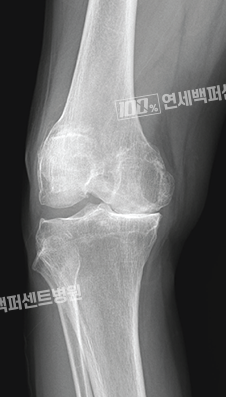

손상된 부분만 선택적으로,

부분 치환술(반치환술)

로봇으로 가능